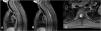

Nervous system involvement is uncommon in granulomatosis with polyangiitis (GPA), a systemic autoimmune disease with episodes of necrotizing vasculitis. It is usually due to the compressive effect of dural or epidural masses. Spinal hemorrhagic presentation is exceptional. A 41-year-old woman diagnosed with GPA presented with three episodes of acute spinal subdural hematoma separated by eight years and ten months, respectively. The symptomatic debut was pain and paresis in all episodes. On all occasions, a lesion compatible with acute spinal subdural hematoma was diagnosed by magnetic resonance imaging (MRI). All episodes were treated conservatively with corticosteroids and immunosuppressants. The patient presented complete neurological recovery in the first two episodes. A mild residual left lower limb paresis remains after the last one. Follow-up MRI was performed after all episodes, and no focal intraspinal lesions were detected. Spinal subdural hemorrhage is a form of manifestation of GPA, either as a debut or in the course of the disease. We describe the third confirmed case of spontaneous spinal hemorrhage secondary to GPA published in the literature and the first with recurrence. Given the extraordinary response to immunosuppressive therapy, a high level of clinical suspicion is necessary to establish treatment as early as possible.

Presentamos un caso en una paciente diagnosticada de granulomatosis con poliangeitis (GPA) que presentó en dos ocasiones separadas por un lapso de 8 años, hematoma subdural agudo espinal con diferentes niveles de afectación en cada uno de los episodios. Se añade una revisión de la literatura. Una mujer de 48 años diagnosticada de GPA, presentó tres episodios de hematoma subdural espinal agudo; separados por un período de tiempo en primer lugar de 8 años y en segundo lugar de 10 meses. Clínicamente, las tres veces se manifestaron con dolor y paresia. En todas las ocasiones, se diagnosticó mediante Resonancia Magnética Nuclear (RMN) la presencia de una lesión compatible con hematoma subdural espinal agudo. Todos los episodios se trataron de forma conservadora con corticoesteroides y Rituximab. La paciente presentó recuperación neurológica completa en los dos primeros episodios. En relación al último; presenta una paresia leve en miembro inferior izquierdo. En todos los episodios se realizó control por RMN y no se detectaron alteraciones intraespinales. La hemorragia subdural espinal es una posible forma de manifestación de la GPA, bien como debut o en el curso de la enfermedad. Es necesario un alto nivel de sospecha clínica para establecer el tratamiento de la forma más precoz posible. Presenta una respuesta extraordinaria a la terapia inmunosupresora. Es posible una recuperación completa a través del tratamiento conservador. Recomendamos un abordaje combinado.